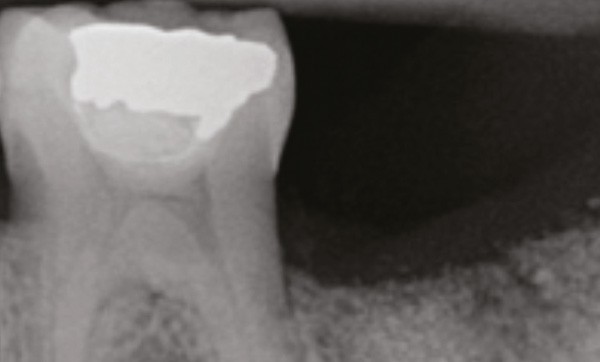

La gestion des sites extractionnels est devenue un prérequis en implantologie orale. En effet, le remplacement dentaire par un implant doit être optimal, tant sur le plan fonctionnel qu’esthétique, et nécessite de maintenir un environnement alvéolaire post-extractionnel compatible avec l’ostéointégration de l’implant. Cet article traite de la place des β-TCP dans ce processus de préservation.

L’extraction d’une dent est un acte traumatique qui, même réalisé avec un minimum de contrainte, déclenche un processus cicatriciel entraînant des modifications morphologiques de l’alvéole [1].

Six mois après l’avulsion, les études cliniques chez l’homme, après réouverture du site d’intervention, montrent une perte osseuse horizontale de 29 à 63 % et une perte osseuse verticale de 11 à 22 %. Cette réduction volumétrique est rapide pendant les 3 à 6 premiers mois [2, 3, 4].

Pour prévenir cette résorption osseuse post-extractionelle, différentes techniques chirurgicales peuvent être réalisées : la régénération osseuse guidée, le comblement alvéolaire, ou les techniques combinées.

Un consensus semble se dégager dans la littérature, qui montre que la préservation alvéolaire limite de manière significative la résorption de la crête alvéolaire après extraction par rapport à une extraction seule. Les dimensions de crête sont également mieux maintenues si la préservation est faite le jour de l’extraction [5, 6, 7].